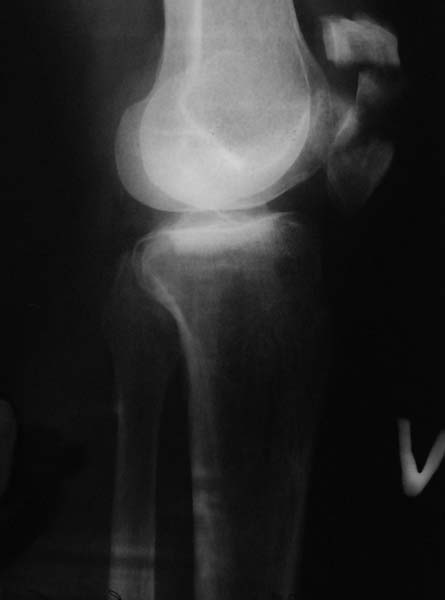

разбита вдребезги надколенная кость

мужчина. 69 лет. 6 осколков, 4-5 из них очень мелкие.